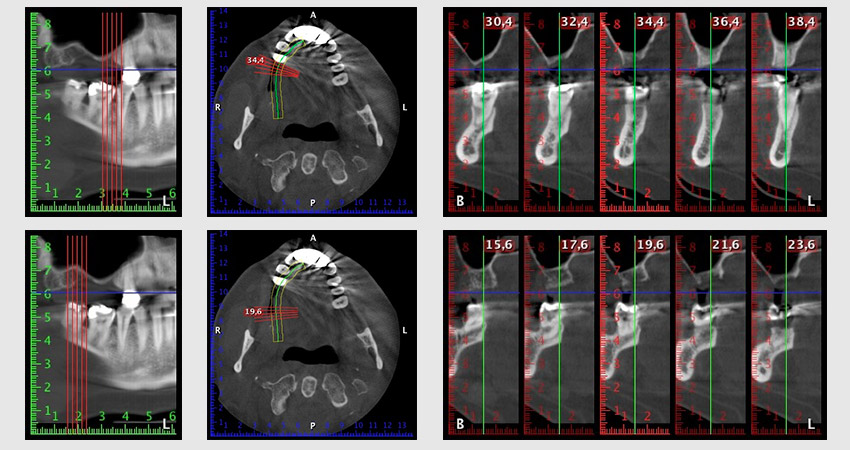

About six months after teeth 16 and 14 were extracted, a digital volume tomography (DVT, Planmeca) examination was performed for planning and risk minimization purposes. It clearly showed that the bone had not regenerated to the desired volume (Fig. 2 to 7).

Image 2 to 7: DVT with greatly reduced horizontal bone volume.

A sinus floor elevation is required in both region 16 and region 14 to guarantee a fixed restoration based on at least two implants. Relatively large-scale bone augmentation is required due to the residual bone volume being extremely low in this case. Major bone augmentation procedures are invasive and linked to higher patient morbidity, as well as being time-consuming and expensive. It is more difficult to predict the results of the treatment and the risk of failure is increased. The patient was informed of the increased risk and was offered a removable solution, which she consistently rejected.

To restrict the augmentation to region 14, and in consultation with the patient, it was planned that implant 16 would be placed, inclined, in the dorso-cranial direction (Fig. 8).

Image 8: DVT with plan of insertion angle for implant 16